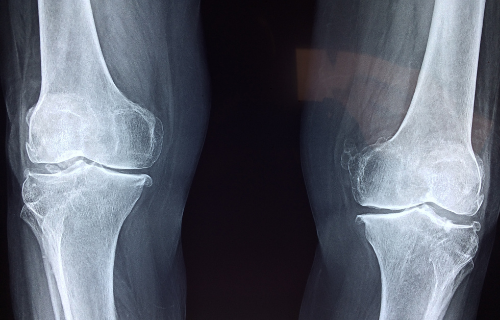

A bone scan is done to check for possible infection or cancer in the bone tissue. It can also be completed to look for fractures and arthritis.

A big benefit of a bone scan is that it is a sensitive test. It can detect very small irregularities in the bone that may not be evident on a regular X-ray. This means that a defect in the bone caused by cancer or infection is more likely to be detected if you have a bone scan than a general X-ray.